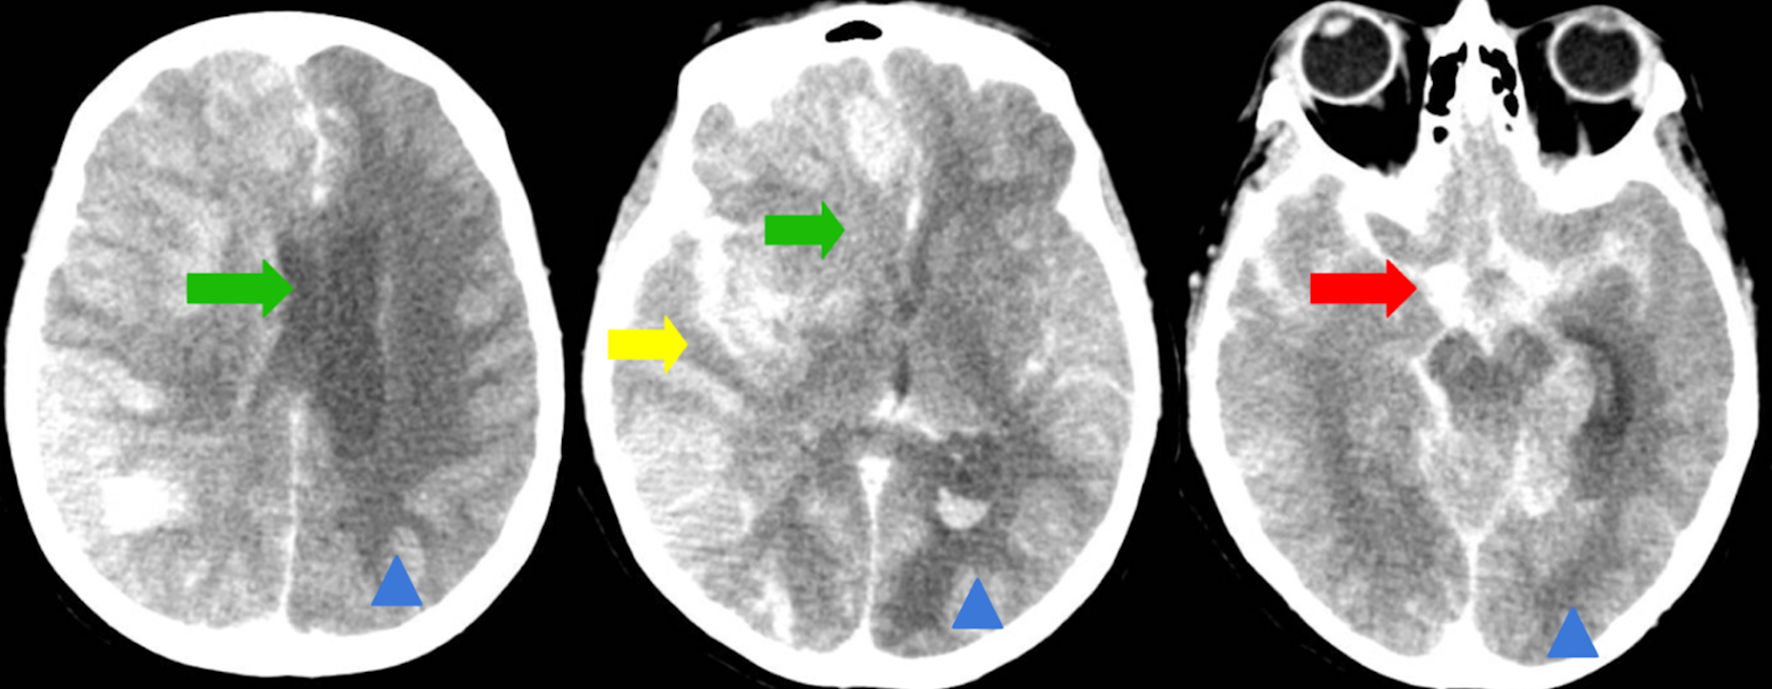

A 63-year-old female with a past medical history of coronary artery disease status post percutaneous coronary intervention to right coronary artery, ischemic cardiomyopathy with ejection fraction of 25%, chronic deep vein thrombosis (DVT) on apixaban with an inferior vena cava filter, multiple past cerebrovascular accidents and previous history of polysubstance abuse was transferred to our center for evaluation of severe anemia and hypotensive shock requiring vasopressor support. Initially, she presented to an outside hospital with profound anemia (hemoglobin 5 g/dL, reference 12.0 - 16.0 g/dL) in the setting of suspected new onset cirrhosis. Gastrointestinal bleeding was suspected, but no source was identified, and hepatology evaluation determined no cirrhosis. She received urgent transfusions of one unit of packed RBCs, two units of plasma, and two units of cryoprecipitate for stabilization. Despite hemodynamic resuscitation, the patient remained encephalopathic, with intermittent unresponsiveness and disorientation. On day 1 of admission, her mental status worsened acutely. She became nonverbal, stopped following commands, stopped visually tracking, and developed right hemiplegia. Neurology consultation was obtained for concern of stroke. On initial neurological examination, her National Institutes of Health Stroke Scale (NIHss) score was 19, indicating a severe stroke syndrome with global aphasia, forced leftward gaze deviation, and right-sided flaccid paralysis. An initial magnetic resonance imaging (MRI) of the brain demonstrated recent ischemic strokes in bilateral cerebral hemispheres, including evolving infarcts in the left temporal and occipital lobes (from prior MRI imaging) and new diffusion-restricted lesions in the right frontal and parietal lobes, without hemorrhage or mass effect (Fig. 1). These acute infarcts coexisted with chronic microvascular ischemic changes and old encephalomalacic infarcts in the bilateral occipital and right parietal lobes (Fig. 1). There were no signs of active infection on urinalysis, and urine toxicology screen was negative. Duplex ultrasonography of the legs showed no DVT to explain an embolic source. Given her anticoagulated status and subacute presentation, thrombolytic therapy was not pursued in addition to not meeting standard time criteria.

Figure 1. Magnetic resonance imaging (MRI) of the brain, axial T2-weighted fluid-attenuated inversion recovery (FLAIR) sequences. Red arrows indicate areas of persistent hyperintensity consistent with evolving acute ischemic infarcts in the bilateral cerebral hemispheres, notably involving the frontal, parietal, and periventricular white matter regions. Additional foci in the right frontal and parietal lobes suggest new acute infarcts. Confluent periventricular hyperintensities are present, compatible with moderate chronic microvascular ischemic disease. Red arrowheads highlight areas of subacute-to-chronic ischemic injury/encephalomalacia, demonstrated by parenchymal volume loss and gliotic signal in the bilateral occipital lobes and right parietal lobe. Multiple small chronic lacunar infarcts are also seen in the corona radiata and centrum semiovale.